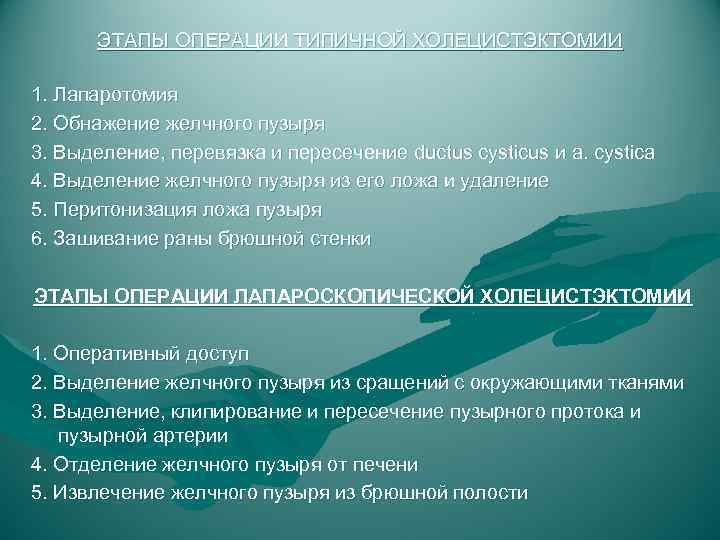

ЭТАПЫ ОПЕРАЦИИ ТИПИЧНОЙ ХОЛЕЦИСТЭКТОМИИ 1. Лапаротомия 2. Обнажение желчного пузыря 3. Выделение, перевязка и пересечение ductus cysticus и a. cystica 4. Выделение желчного пузыря из его ложа и удаление 5. Перитонизация ложа пузыря 6. Зашивание раны брюшной стенки ЭТАПЫ ОПЕРАЦИИ ЛАПАРОСКОПИЧЕСКОЙ ХОЛЕЦИСТЭКТОМИИ 1. Оперативный доступ 2. Выделение желчного пузыря из сращений с окружающими тканями 3. Выделение, клипирование и пересечение пузырного протока и пузырной артерии 4. Отделение желчного пузыря от печени 5. Извлечение желчного пузыря из брюшной полости

ЭТАПЫ ОПЕРАЦИИ ТИПИЧНОЙ ХОЛЕЦИСТЭКТОМИИ 1. Лапаротомия 2. Обнажение желчного пузыря 3. Выделение, перевязка и пересечение ductus cysticus и a. cystica 4. Выделение желчного пузыря из его ложа и удаление 5. Перитонизация ложа пузыря 6. Зашивание раны брюшной стенки ЭТАПЫ ОПЕРАЦИИ ЛАПАРОСКОПИЧЕСКОЙ ХОЛЕЦИСТЭКТОМИИ 1. Оперативный доступ 2. Выделение желчного пузыря из сращений с окружающими тканями 3. Выделение, клипирование и пересечение пузырного протока и пузырной артерии 4. Отделение желчного пузыря от печени 5. Извлечение желчного пузыря из брюшной полости

ЭТАПЫ ОПЕРАЦИИ ТИПИЧНОЙ ХОЛЕЦИСТЭКТОМИИ ( от шейки) 1. Лапаротомия 2. Обнажение желчного пузыря 3. Выделение, перевязка и пересечение ductus cysticus и a. cystica 4. Выделение желчного пузыря из его ложа и удаление 5. Перитонизация ложа пузыря? ? ? 6. Зашивание раны брюшной стенки ЭТАПЫ ОПЕРАЦИИ ТИПИЧНОЙ ХОЛЕЦИСТЭКТОМИИ ( от дна) 1. Лапаротомия 2. Обнажение желчного пузыря 3. Выделение желчного пузыря из его ложа и удаление 4. Выделение, перевязка и пересечение ductus cysticus и a. cystica 5. Перитонизация ложа пузыря? ? ? 6. Зашивание раны брюшной стенки

ЭТАПЫ ОПЕРАЦИИ ТИПИЧНОЙ ХОЛЕЦИСТЭКТОМИИ ( от шейки) 1. Лапаротомия 2. Обнажение желчного пузыря 3. Выделение, перевязка и пересечение ductus cysticus и a. cystica 4. Выделение желчного пузыря из его ложа и удаление 5. Перитонизация ложа пузыря? ? ? 6. Зашивание раны брюшной стенки ЭТАПЫ ОПЕРАЦИИ ТИПИЧНОЙ ХОЛЕЦИСТЭКТОМИИ ( от дна) 1. Лапаротомия 2. Обнажение желчного пузыря 3. Выделение желчного пузыря из его ложа и удаление 4. Выделение, перевязка и пересечение ductus cysticus и a. cystica 5. Перитонизация ложа пузыря? ? ? 6. Зашивание раны брюшной стенки

ЭТАПЫ ЛАПАРОСКОПИЧЕСКОЙ ХОЛЕЦИСТЭКТОМИИ 1. Оперативный доступ 2. Выделение желчного пузыря из сращений с окружающими тканями 3. Выделение, клипирование и пересечение пузырного протока и пузырной артерии 4. Отделение желчного пузыря от печени 5. Извлечение желчного пузыря из брюшной полости

ЭТАПЫ ЛАПАРОСКОПИЧЕСКОЙ ХОЛЕЦИСТЭКТОМИИ 1. Оперативный доступ 2. Выделение желчного пузыря из сращений с окружающими тканями 3. Выделение, клипирование и пересечение пузырного протока и пузырной артерии 4. Отделение желчного пузыря от печени 5. Извлечение желчного пузыря из брюшной полости